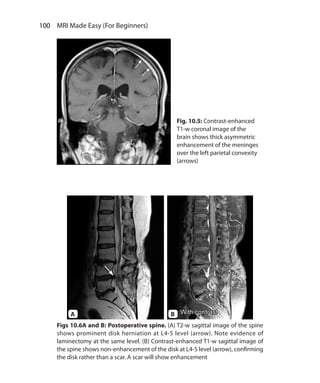

state sequences 40

Postoperative spine 100f

Pre-excitation refocused steady-state

sequences 40

Index.indd 206 14-09-2012 17:50:22

207 Index

Primary sclerosing cholangitis 188,

188f